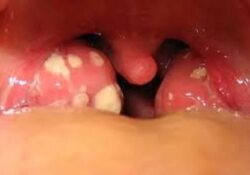

¿Sabes que son las piedras de las amígdalas? Descubre que es lo que pueden producir

Hay muchísimos videos de Internet donde se extirpan barritos y espinillas gigantes. Ahora circulan videos de piedras que se extirpan en las amígdalas. Resulta que gracias a la popularidad de estos videos, mucha gente está descubriendo por primera vez lo… Continuar leyendo →